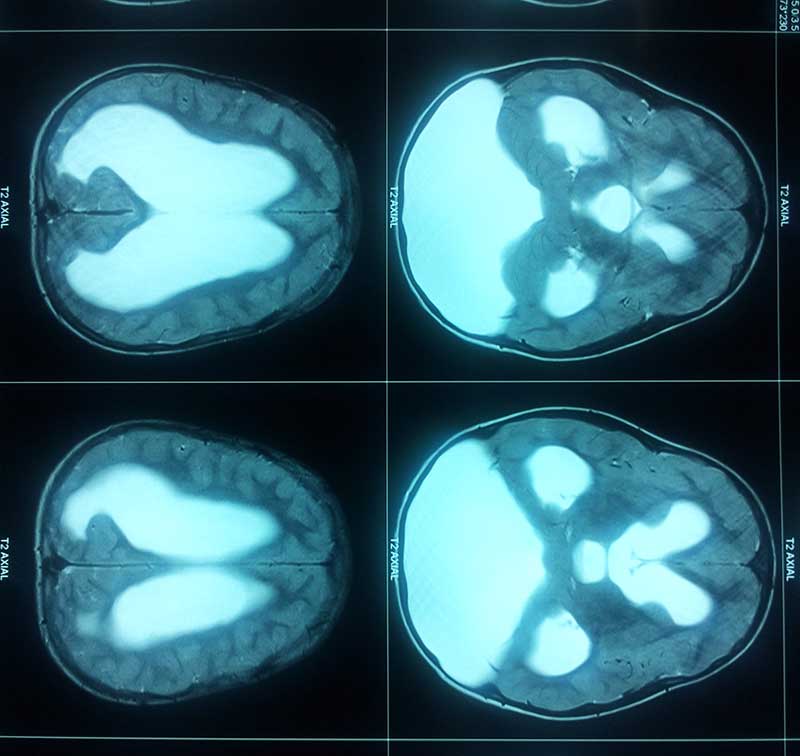

Dandy Walker Malformation

dandy walkar pre op mri

• dandy walkar pre op mri